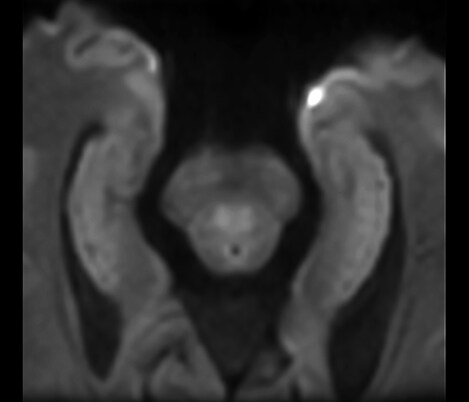

Da colaboração O Dr. Tetsuya Yoneda, Universidade de Kumamoto, Japão, fala sobre a sua colaboração com a Philips numa técnica denominada SWIp desenvolvida para a imagiologia com suscetibilidade ponderada.

...à prática clínica O Dr. Chip Truwit, Hennepin County Medical Center, Minneapolis, EUA, explica como o SWIp se tornou parte integrante de todos as exames de lesões de RM.